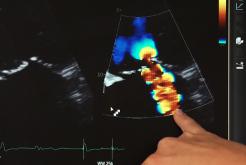

Insuffisance mitrale : l'échographie en ligne de fuite

En cas d'insuffisance mitrale, l'échographie est l'examen clef pour évaluer la sévérité de la régurgitation et orienter la stratégie thérapeutique…